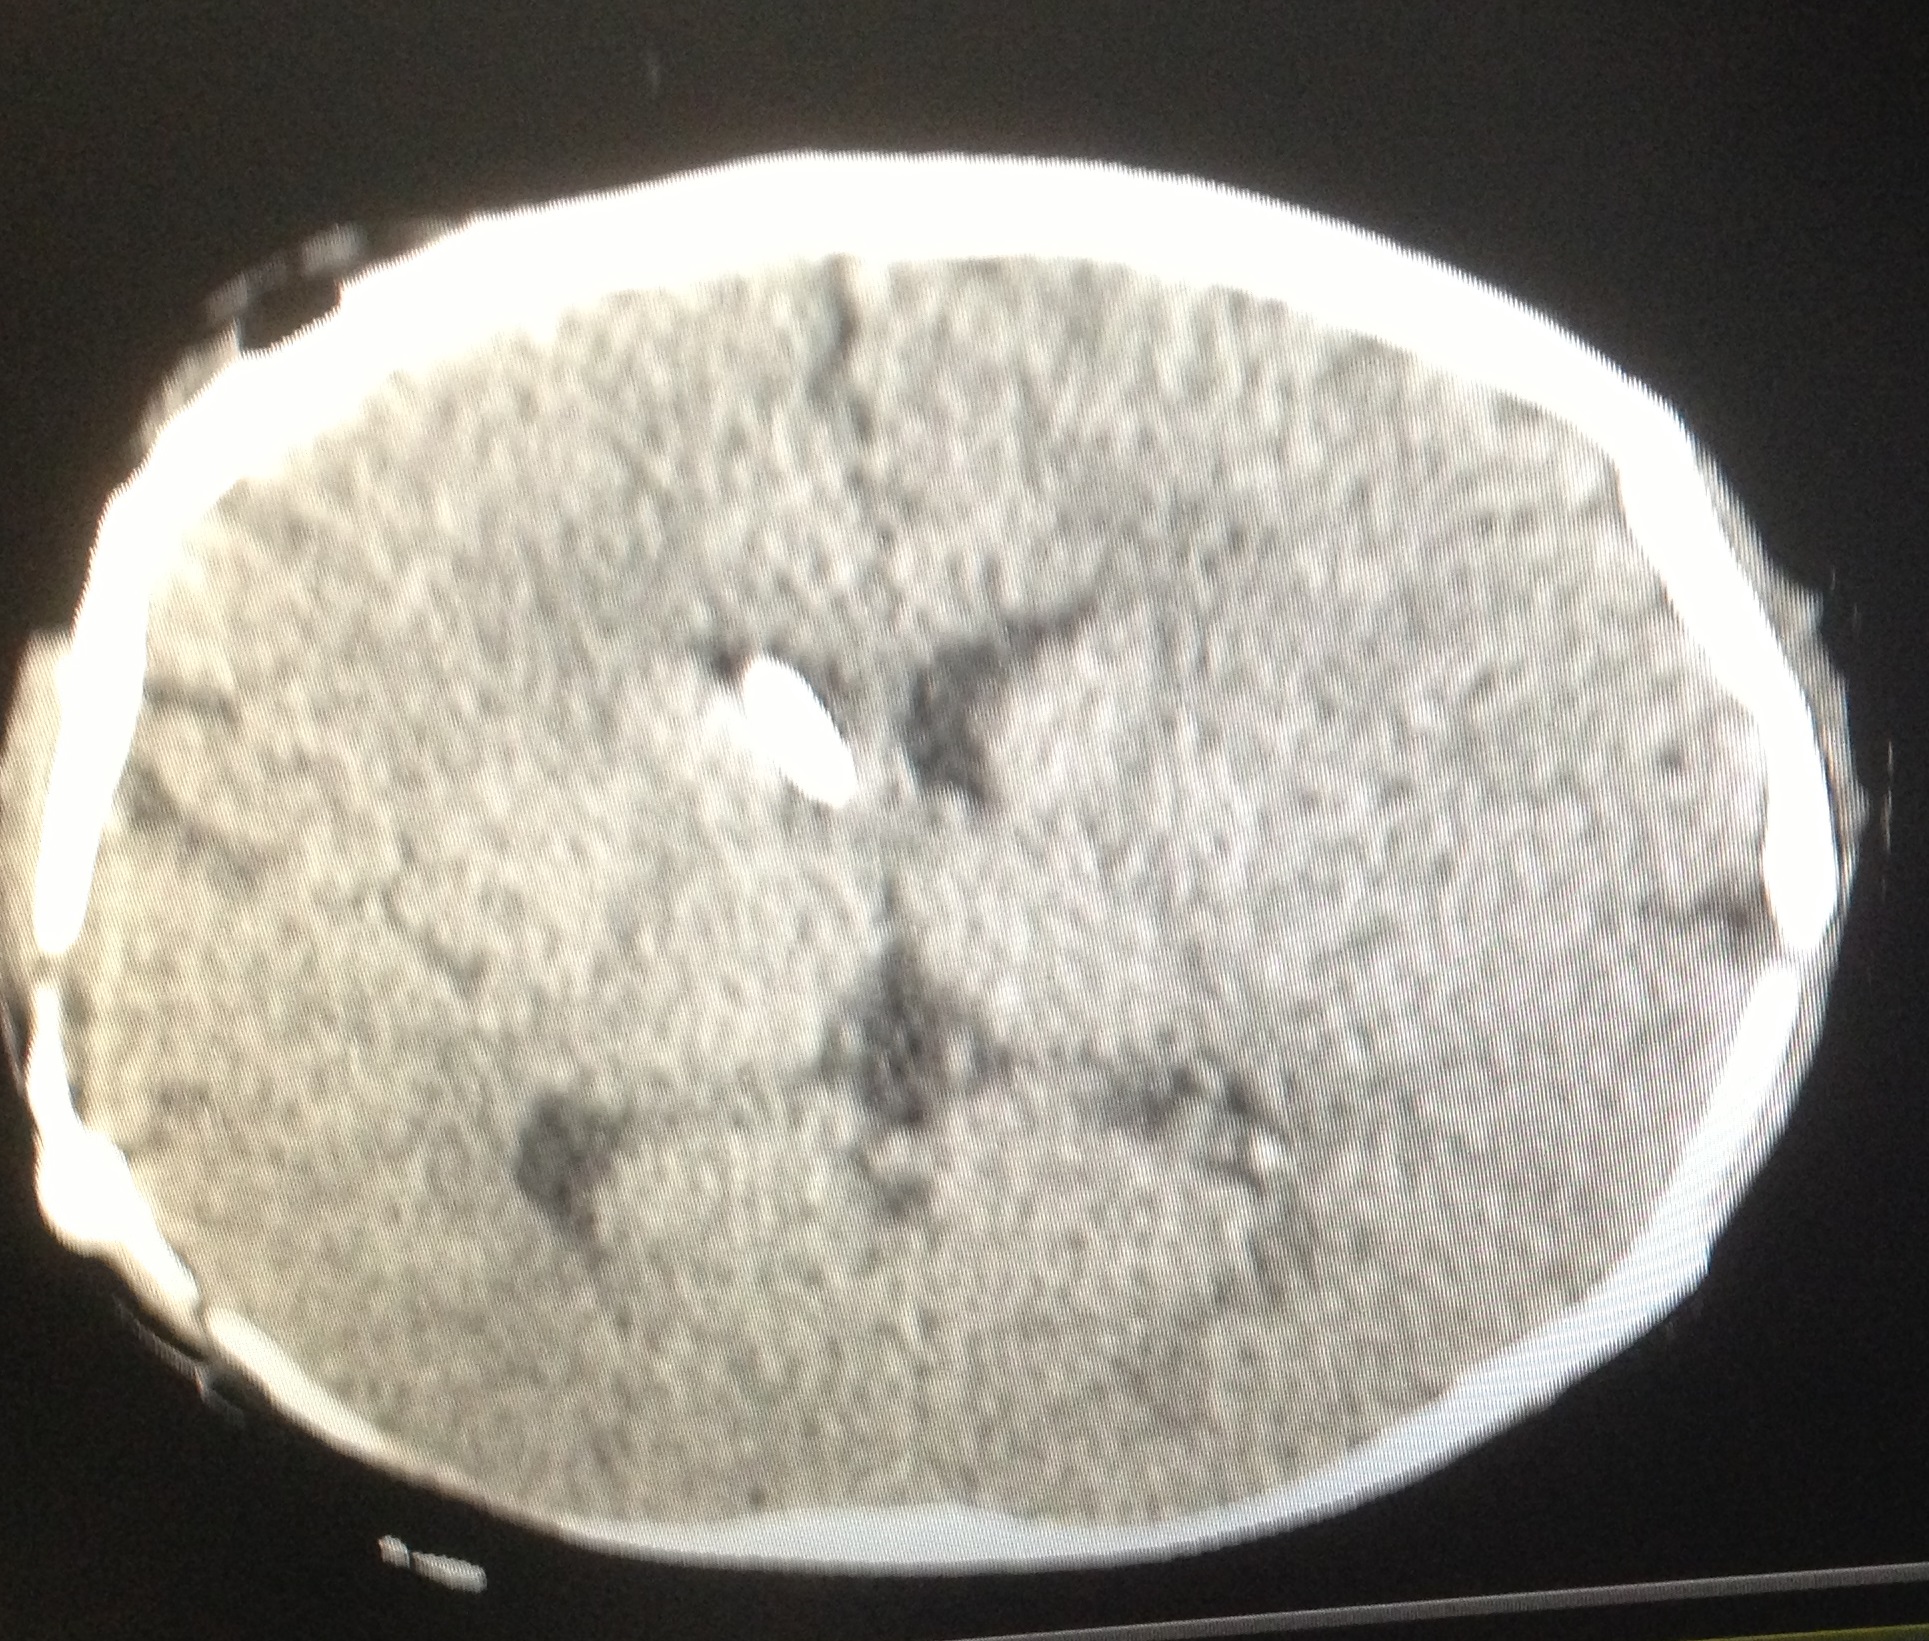

The signs and symptoms of shunt dysfunction are related to high intracranial pressure most commonly including headache, nausea, vomiting, bulge fontanel, irritability, sunset eye. Increased ventricular diameter in comparison to prior studies, increased temporal horns width, sulcus effacement and rounding of 3rd ventricle are common findings in neuroimaging studies during shunt malfunction (Figure 1). However, stable ventricular dimensions on serial imaging studies (Figure 2) may wrongly be interpreted as normal shunt function [4].

Figure 2: A. Slit like ventricle after 9 months of shunting in an infant with congenital hydrocephalus; the child was stable without any symptoms. B. One year later he was admitted with persistent vomiting and ptosis. The brain CT shows no obvious change in the size of ventricle. His symptoms were recovered after shunt revision due to proximal catheter obstruction.